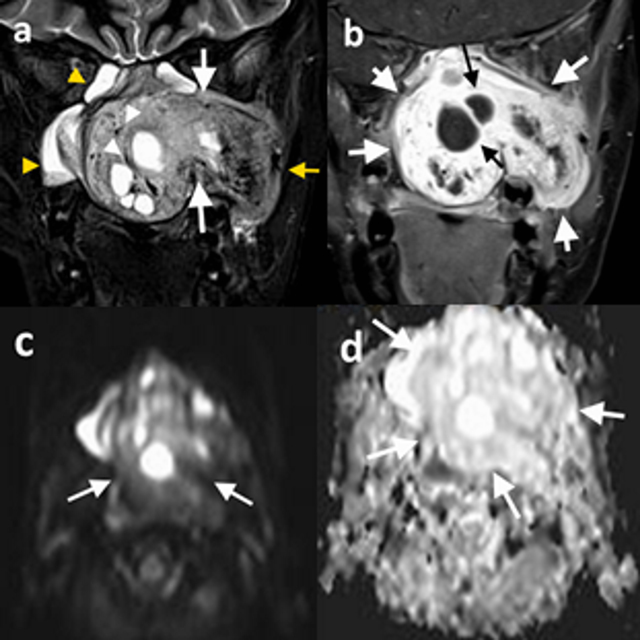

Figure 1

13-year-old male patient (patient 5), (a) coronal T2-weighted precontrast, (b) coronal T1-weighted postcontrast, (c) DWI, and (d) ADC map demonstrate a left-sided nasopharyngeal mass which enlarges the ipsilateral pterygopalatine fossa (a, white arrows) and extends into the temporal fossa (a, yellow arrow). The mass is hyperintense on T2-weighted image (a) and exhibits significant contrast enhancement (b). Diffusion-weighted images (c) showed no diffusion restriction, and the lesion has high signal intensity on the ADC map (d). The tumor demonstrates internal cystic components (b, black arrows) and signal-void regions (a, white arrowheads). Image a demonstrates inflammatory signal changes in maxillary and sphenoid sinuses (yellow arrowheads).